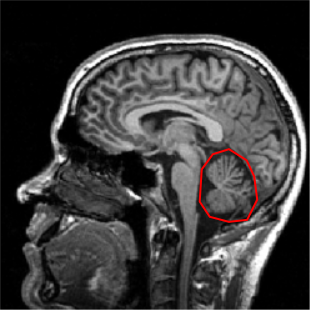

Cerebellum

- Two hemispheres, several lobes divided by fissures

- Neurons in sheets, called cortex

- Receives sensory input from spinal cord, motor info from cerebral cortex, balance info from inner ear and vestibular organs

- Primarily used for motor control, particularly in making postural adjustments and in fine-tuning movements

- Essential for the coordination, planning of movements, learning motor tasks and storing this information

Cerebellum is latin for 'little brain.'

The cerebellum is located dorsal to the brainstem.

It has two…

Neurons form cortical sheets like in the cerebral hemispheres.

Receives…

fyi: The MRI image is J. Ackman's brain from 2009!

Cerebellum is latin for ‘little brain’, and it does have a striking organization with lobes and fissures similar to the folding of the cerebral cortex to increase surface area and packing density of neuronal interconnections. You can see here its main cell body layer, obvious in this purple nissl stain for cell bodies here. It’s in this layer where you will find the beautiful purkinje neurons that we saw images of in lecture 01.